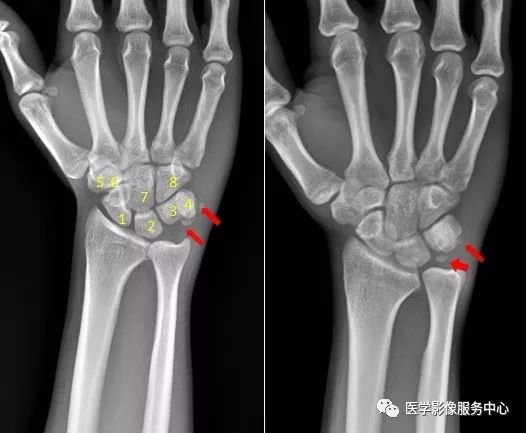

腕关节

1.舟骨  2.月骨  3.三角骨  4.豌豆骨  5.大多角骨  6.小多角骨  7.头状骨  8.钩骨右腕关节近三角骨、豆状骨内侧见多个游离骨碎片影,小碎骨片分离移位。考虑为,右腕关节三角骨,豌豆骨粉碎性骨折。

右侧桡骨远端可见不规则透亮骨折线,并累及关节面。右侧桡骨远端骨折尺骨茎突见游离骨碎片影。右侧尺骨茎突骨折。肘关节